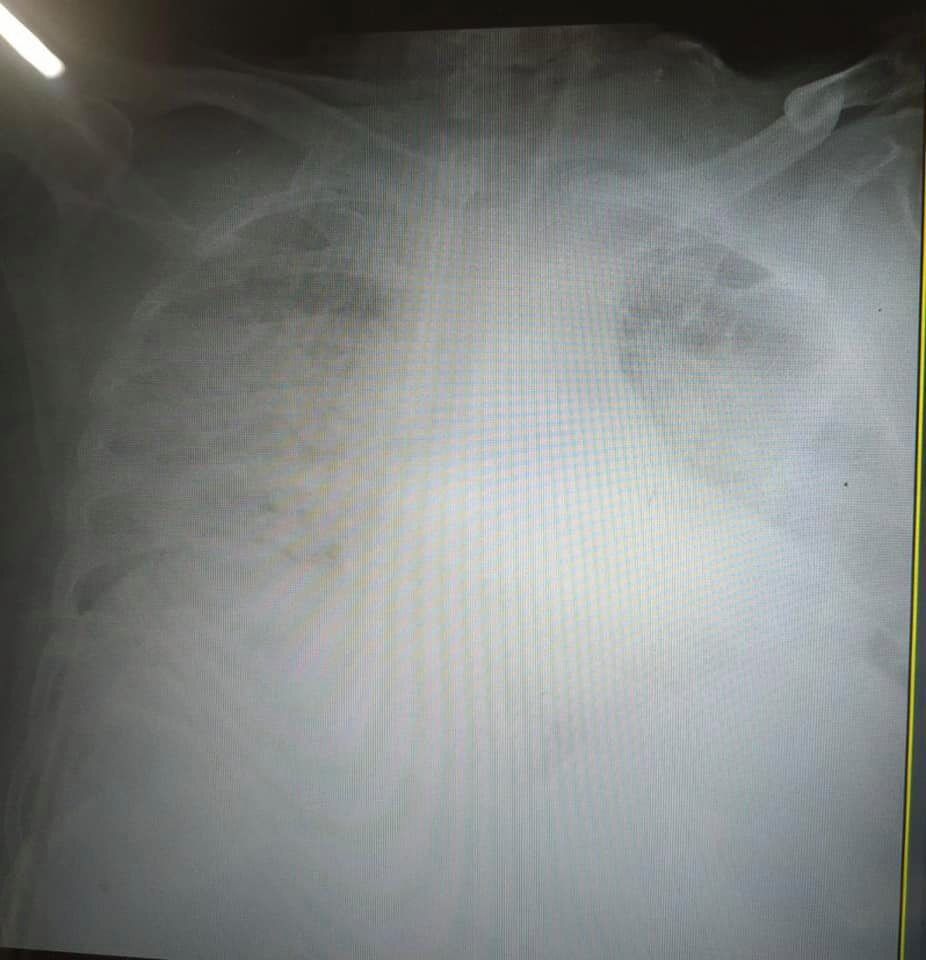

Врач показала "самые страшные" легкие больного COVID-19

Украинская журналистка Ирина Заславец показала фото рентгена легких, пораженных коронавирусной болезнью (COVID-19).

Снимки она опубликовала в Facebook после общения с главой реанимации Клинической больницы скорой медицинской помощи Львова Натальей Матолинец.

"Это одни из самых страшных легких, которые я видела в жизни", – отметила врач.